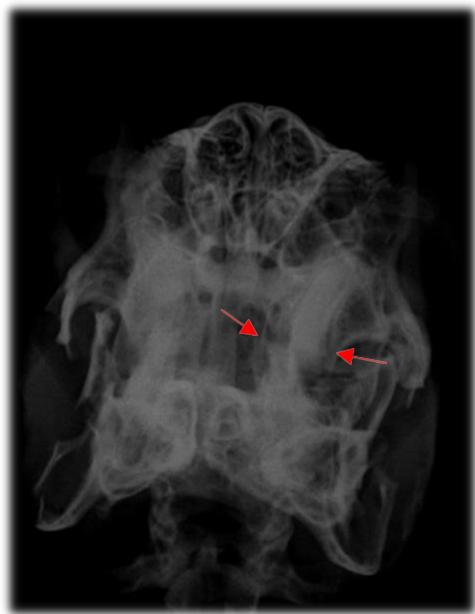

Fig. 8: Radiografia de crânio projeção rostro caudal. Visualização de pontas dentárias evidenciadas pelas setas vermelhas Fig. 9: Radiografia de crânio projeção dorso ventral. Leve desalinhamento dentário na borda medial do ramo mandibular direito, sobrepuljando a linha de referência anatômica amarela, evidenciado em vermelho Fonte: Arquivo pessoal do autor Fig. 10: Radiografia de crânio projeção latero lateral visualização de crescimento dentário dos pré molares e molares sobre a mesa oclusal (linha amarela ${ \mathsf { n } } ^ { \mathsf { o } } \ { \mathsf { 1 } } \ -$ traçada do início do palato duro ao terço inferior da bula timpânica) e também visualização de crescimento da coroa de reserva acima da linha amarela $\mathsf { n } ^ { \circ } \mathsf { \Lambda } _ { 2 } ^ { }$ que vai do osso nasal ao osso occipital (sugerindo crescimento retrógrado), evidenciado pelas setas vermelhas.